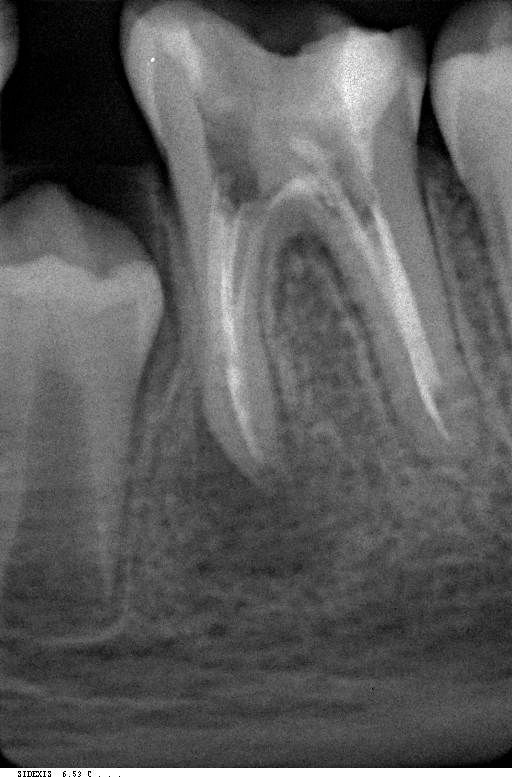

*Далее-берутся рентгенограммы. Во время Эндодонтического лечения берутся несколько наборов рентгенограмм. В начале по крайней мере два необходимы.

До лечения Во время лечения Спустя 6 мес

Для проверки правильности процедур берется одна или несколько “контрольных” рентгенограмм. Несмотря на то, что многие считают Эндодонтическое лечение завершенным после обтурации корневого канала, есть по крайней мере два одинаково важных шага для здоровья и долголетия зуба.